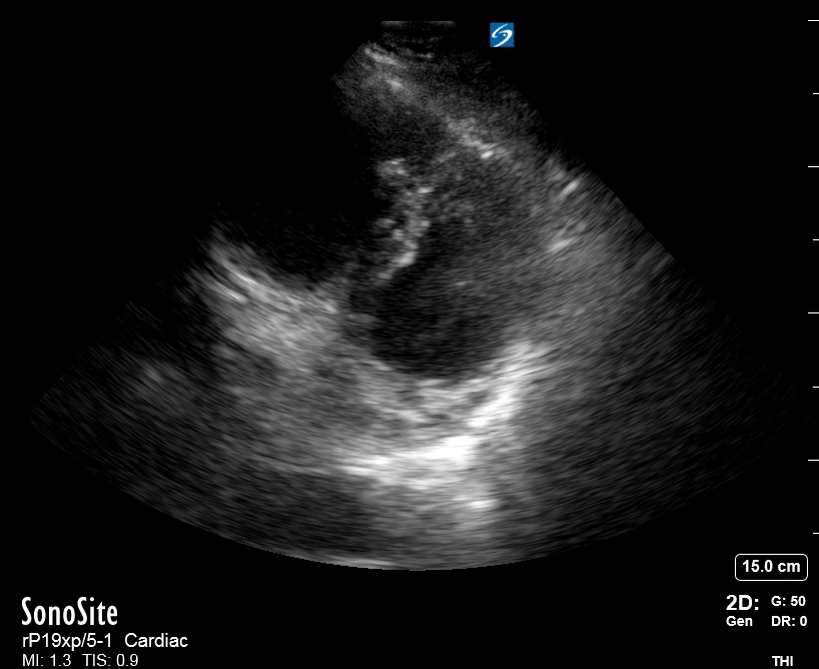

SIGNIFICANTLY IMPAIRED / DILATED LV

A severely depressed LV contractility, particularly when paired with a plethoric IVC or lung B-lines, indicates systolic heart failure. Chronically raised afterload can lead to severe dilation of the LV.

A “non-coordinated myocardial activity” can be recognised during cardiac arrest, and its prognosis is beyond poor.

HYPERDYNAMIC

In contrast, hyperdynamic states are associated with decreased afterload and are classically found in patients with sepsis or severe hypovolaemia. A hyperdynamic heart should be accompanied by a small, collapsing IVC. Moreover, is essential to remember that tachycardic is not the same as hyperdynamic, as the latter is a measure of contractile activity and emptying. A tachycardic heart is not necessarily hyperdynamic.